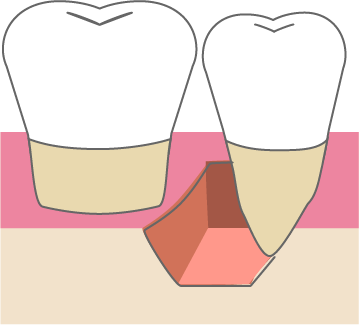

歯周組織再生療法は施術の難易度が高く、ほとんどの歯科では扱っていない内容です。